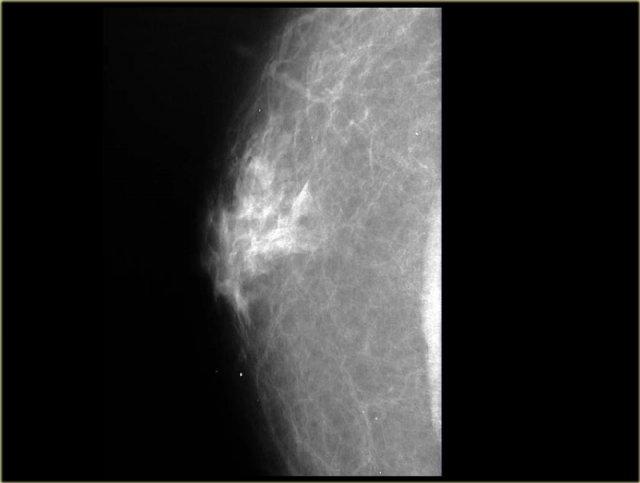

Bên trái là hình chụp nhũ ảnh vú nam giới với dạng gynecomastia thể nốt tuyến.

Có một vùng đậm độ hình quạt tỏa ra từ núm vú.

Tổn thương có thể nổi bật hơn ở góc phần tư trên ngoài và, quan trọng hơn, nó hòa lẫn vào mô mỡ xung quanh.

Nếu nhìn nhũ ảnh bên trái như là vú của một phụ nữ thay vì đàn ông, bạn có thể nhận định đây là một khối bờ không rõ và kết luận đây là tổn thương ác tính.

Tuy nhiên, ở nam giới, bờ không rõ này lại là dấu hiệu của gynecomastia.

Gynecomastia là sự tăng sinh đồng thời của các ống tuyến và mô đệm mà không có bao xơ bao quanh, do đó tổn thương phải hòa lẫn vào mô mỡ xung quanh.